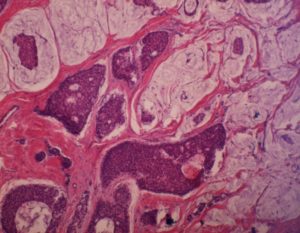

Подобный диагноз ставят в 80 % случаев, когда пациентка сталкивается с раком груди. Инвазивная карцинома — это понятие, которое объединяет целый ряд различных новообразований. Их делят на следующие подвиды:

- Инвазивная протоковая карцинома характеризуется тем, что перерожденные клетки образуются в молочных каналах, откуда распространяются в прилегающие ткани. На следующих стадиях атипичные структуры проникают в систему кровообращения.

- Инвазивную дольковую карциному отличает локализация. Этот тип распространен меньше предыдущего (15 % случаев). Изначально новообразование захватывает дольчатую структуру железы, позднее переходит на близлежащие ткани.

Также встречаются неспецифические типы, но все подвиды заболевания разделяют на стадии от 0 до IV в зависимости от размера опухоли и наличия метастазов. Другим критерием становится степень дифференцировки:

- при высоком показателе опухоли сохраняют отличительные черты нормальных тканей, а распространение происходит медленно;

- при низком разница выражена ярче, а метастазирование отличается скоростью.

Показатель принято определять латинской буквой g в сочетании с цифрой, и чем больше значение, тем неблагоприятнее прогнозы.

Gx обозначает, что стадию установить не удается, а g1 и g2 определяют высоко- и среднедифференцированные опухоли.

Классификация g3 инвазивной карциномы неспецифического типа подразумевает, что показатель низок; на следующем этапе (g4) клетки утрачивают все свойства нормальных.